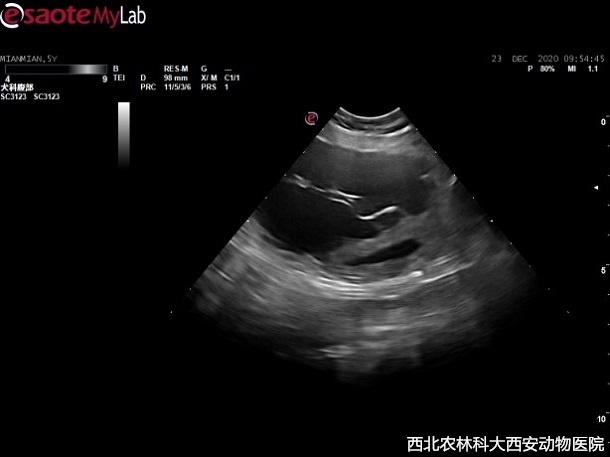

患寵:薩摩耶犬,雄性,5歲,近期出現(xiàn)大小便排泄困難,尿頻,尿血,大便時有明顯痛感前來就診,曾在他院進(jìn)行X線檢查,懷疑前列腺囊腫或膀胱腫瘤,因不能確診治療轉(zhuǎn)診至我院。

查體:體溫38.4℃,脈搏102次/分,呼吸29次/分。精神尚可,被毛尚可,食欲減退,排尿帶血,排便困難,觸診后腹部有一明顯不規(guī)則占位待查。

輔助檢查:主人自帶腹部平片顯示前列腺增大,膀胱前列腺區(qū)域有一明顯占位待查。超聲提示:前列腺增生且伴有囊腫,緊鄰前列腺和膀胱可見無回聲異常囊性占位,與周圍組織有聯(lián)系,疑似粘連見(圖1)。

圖一